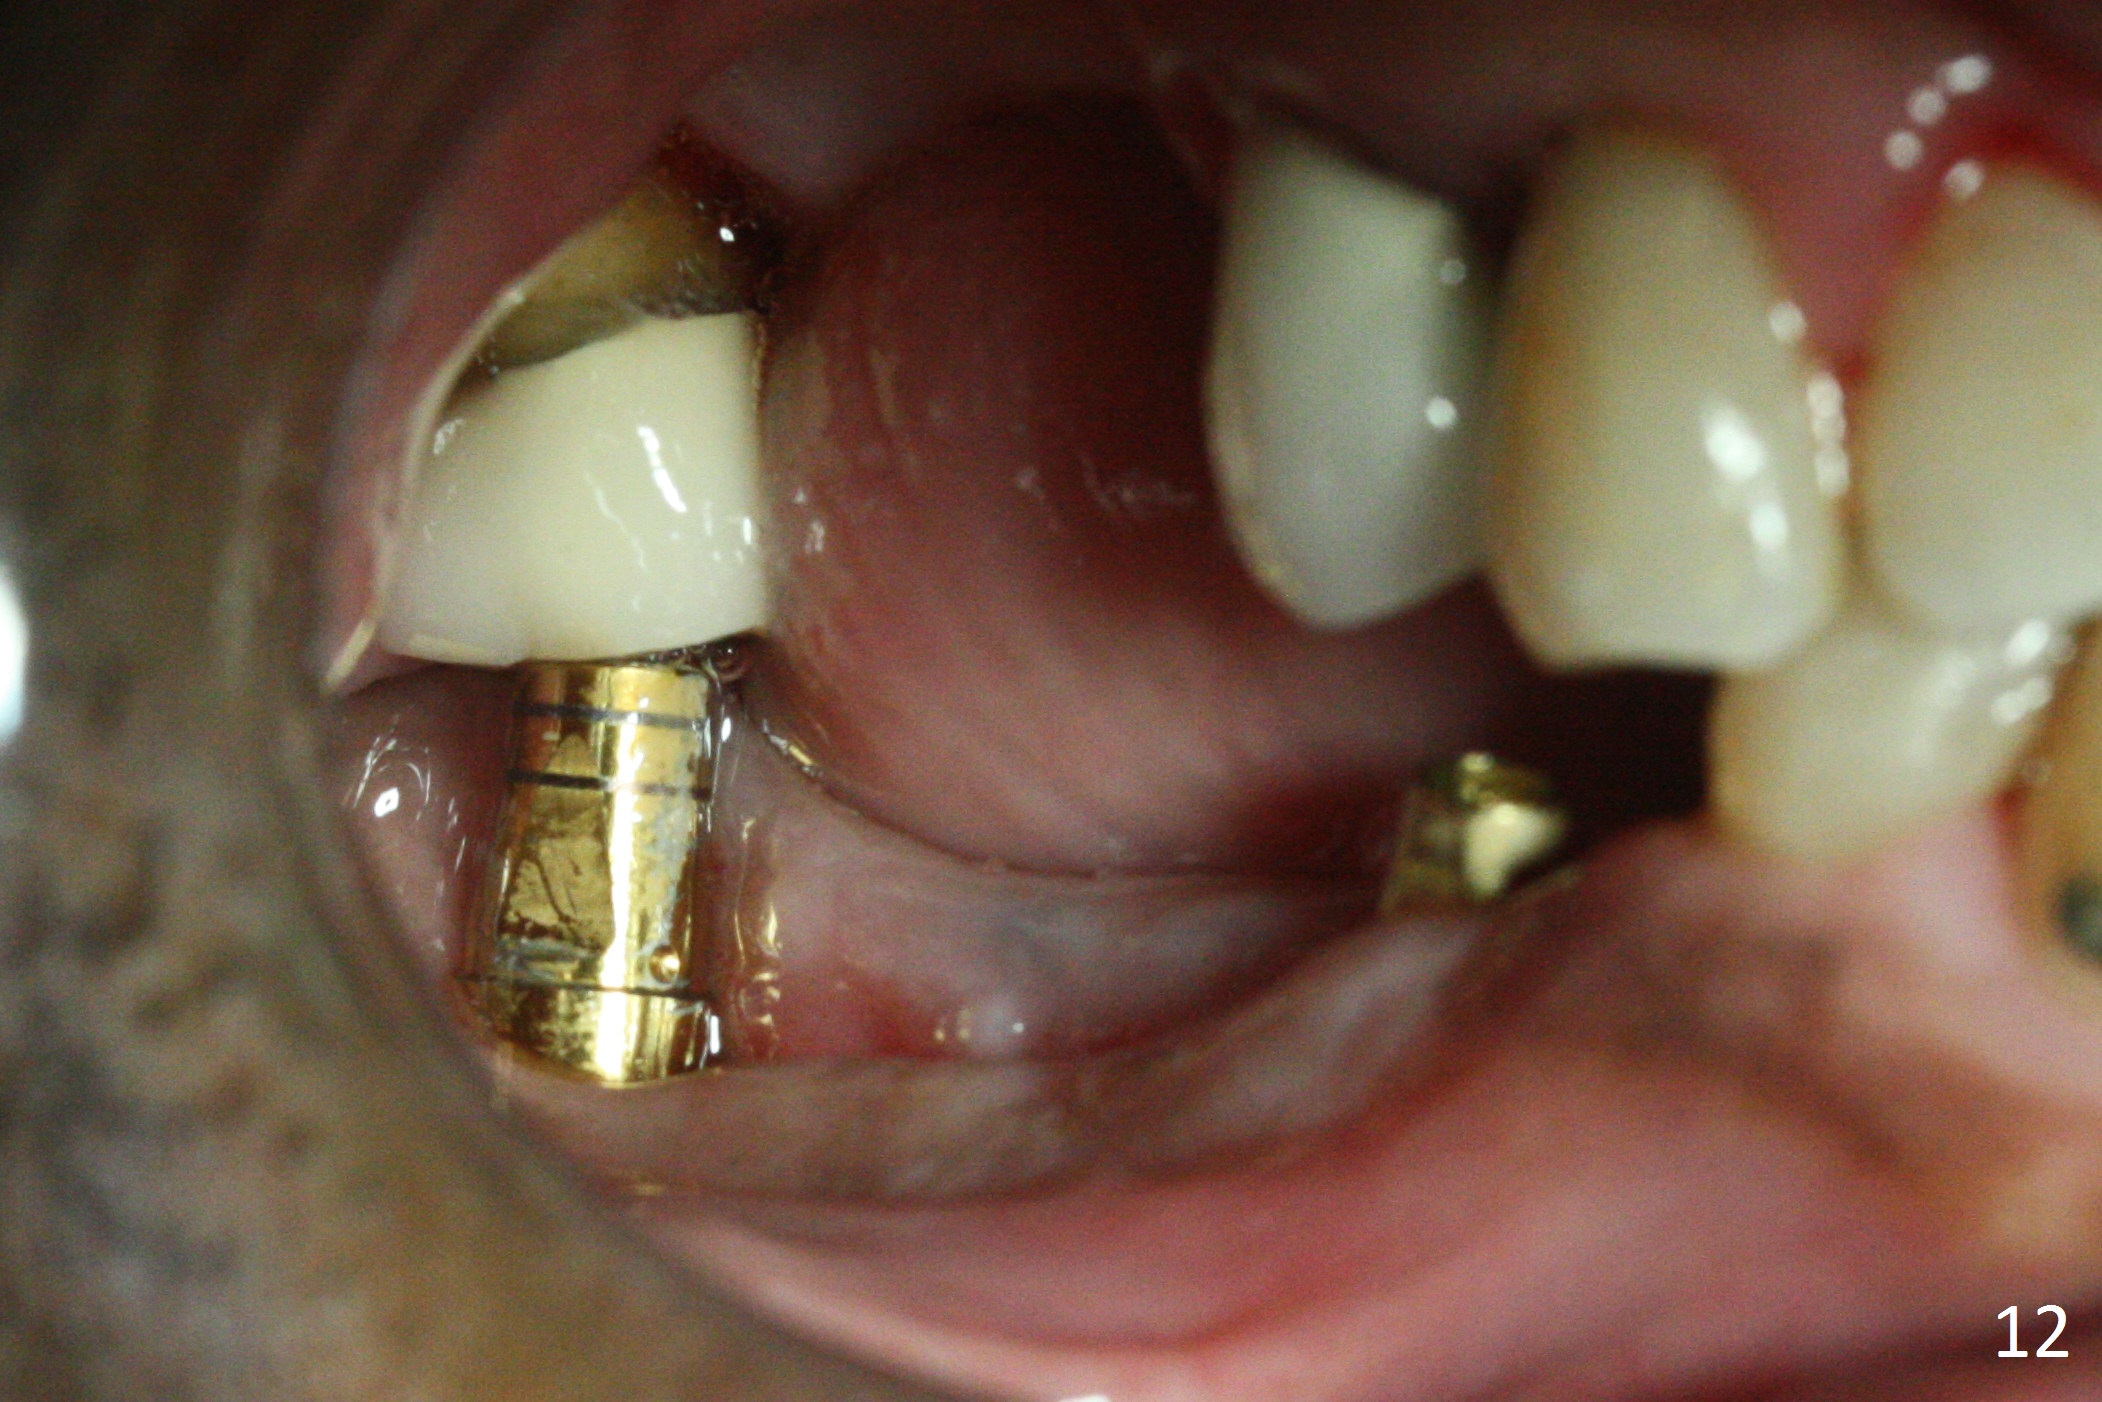

The patient is doing fine postop. He returns asymptomatic 5 weeks postop. There is minimal gingival erythema lingual to the non-resorbable membrane (Fig.10 C). After removal of plaque around the abutments, the membrane is removed (Fig.11). Two weeks later, the wound has healed (Fig.12). The abutment at #29 is basically buried, while the one at #31 is covered by the lingual gingiva.